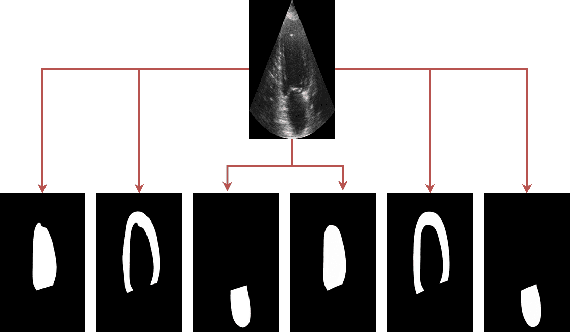

Abstract:In recent years, deep learning has rapidly become a method of choice for the segmentation of medical images. Deep Neural Network (DNN) architectures such as UNet have achieved state-of-the-art results on many medical datasets. To further improve the performance in the segmentation task, we develop an ensemble system which combines various deep learning architectures. We propose a two-layer ensemble of deep learning models for the segmentation of medical images. The prediction for each training image pixel made by each model in the first layer is used as the augmented data of the training image for the second layer of the ensemble. The prediction of the second layer is then combined by using a weights-based scheme in which each model contributes differently to the combined result. The weights are found by solving linear regression problems. Experiments conducted on two popular medical datasets namely CAMUS and Kvasir-SEG show that the proposed method achieves better results concerning two performance metrics (Dice Coefficient and Hausdorff distance) compared to some well-known benchmark algorithms.